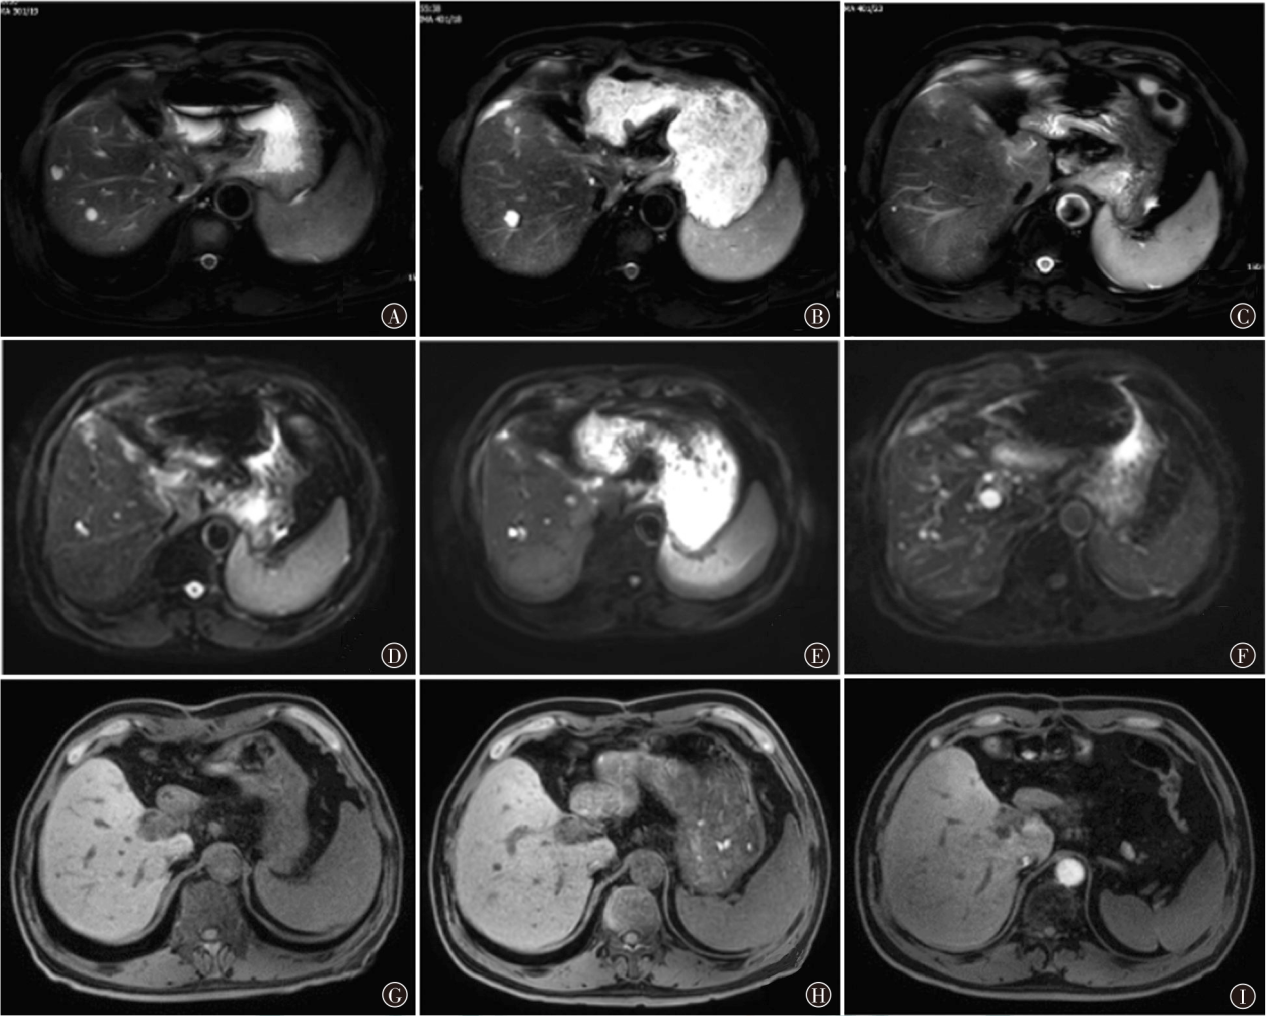

肝内胆管癌(ICC)是消化系统常见肿瘤,起源于肝内胆管上皮细胞,其发病隐匿,早期诊断困难,恶性程度高,预后极差。索凡替尼为我国自主研发的血管内皮生长因子受体酪氨酸激酶抑制剂,此前主要用于非胰腺神经内分泌瘤患者的治疗,最近研究发现其在胆道肿瘤中疗效确切,现报道1例索凡替尼靶向联合卡培他滨+奥沙利铂治疗ICC术后患者,以期为ICC的临床治疗提供参考。